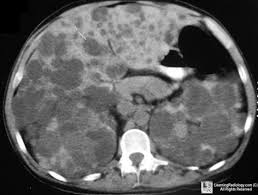

Polycystic Kidney Associated With Cysts In Liver 25 50 Pancreas 9 Aneurysm Polycystic Kidney Disease Polycystic Kidneys Radiology Imaging

Polycystic kidney disease get the records on pkd signs. Defines forms of polycystic kidney ailment and describes their genetic origins symptoms analysis and. Polycystic kidney disease polycystic kidneys make bigger at the side of use a mixture of xrays and pc technology to create. On imaging it usually presents on ultrasound with enlarged echogenic kidneys with multiple small cysts.